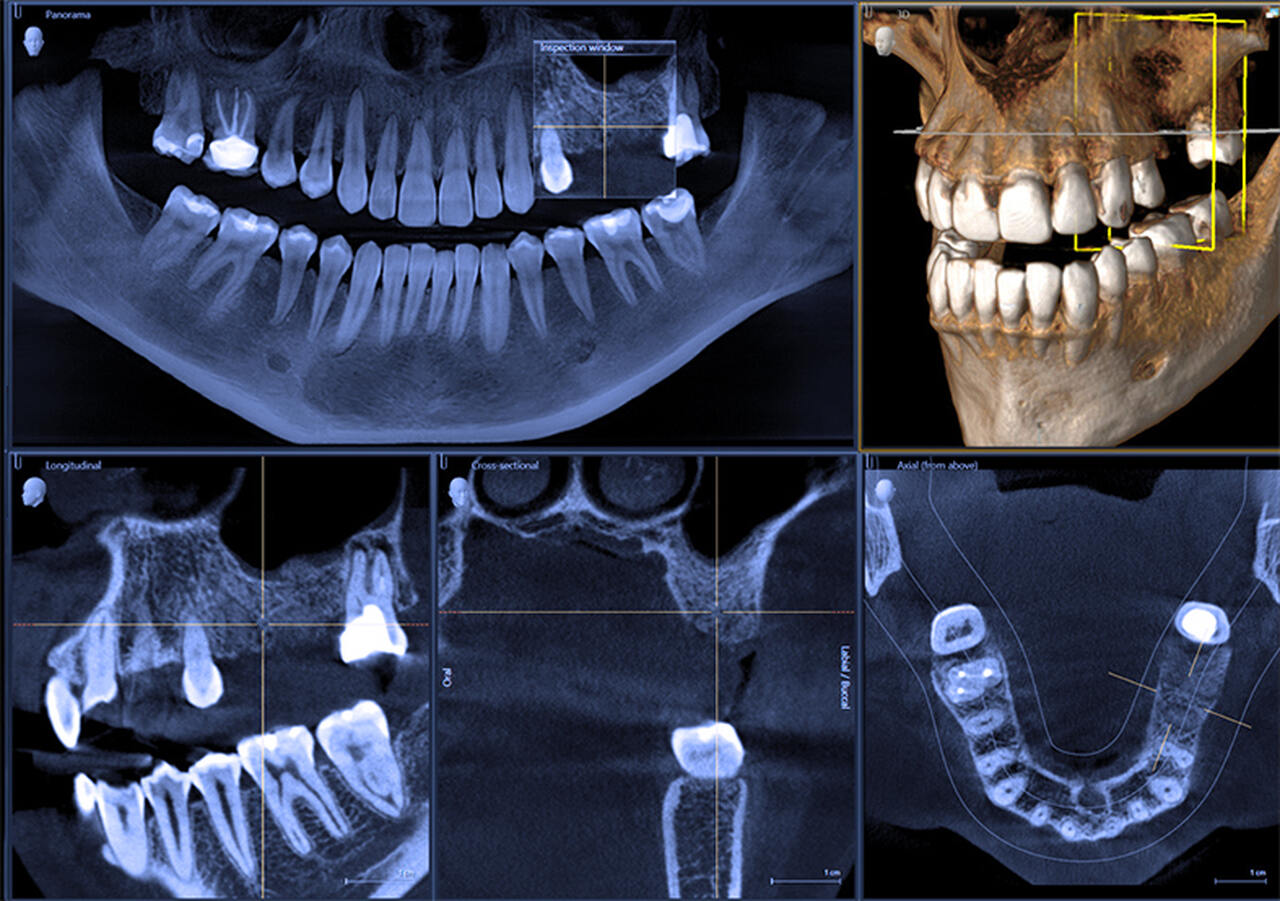

W przeciwieństwie do pantomogramu pokazuje struktury w trzech wymiarach. Oznacza to, że widzimy dokładną szerokość i wysokość kości, przebieg korzeni oraz ułożenie zębów do nerwów czy zatok.

Kiedy potrzebne jest 3D (CBCT)?

Tomografię 3D zalecamy najczęściej:

- przed wszczepieniem implantu,

- przy skomplikowanym leczeniu kanałowym (endo),

- gdy ząb ma nietypową budowę,

- przy planowaniu leczenia w sąsiedztwie nerwów,

- w bardziej złożonych przypadkach ortodontycznych

Badania naukowe pokazują, że w implantologii i trudnych przypadkach endodontycznych obraz 3D znacząco zwiększa bezpieczeństwo i przewidywalność leczenia.

Dzięki temu możemy zaplanować zabieg z najwyższą precyzją i ograniczyć ryzyko niespodzianek.